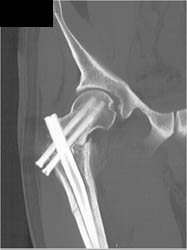

Soft Tissue Swelling